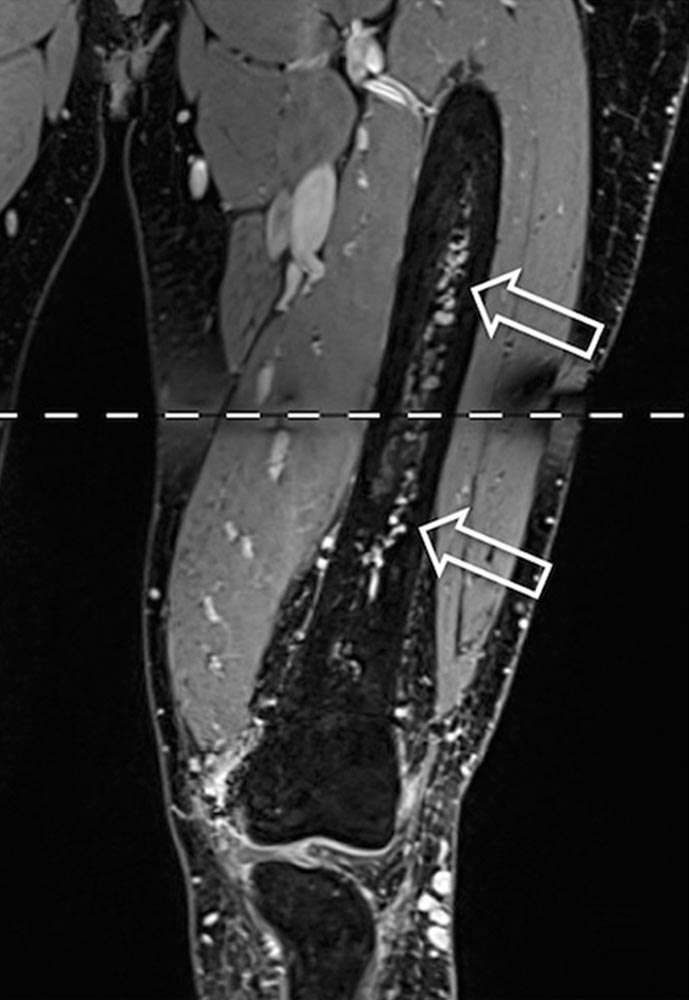

Durch die vorliegenden Shunts kann diese Schwellung mit einem Pulsieren sowie einer zunehmenden, sich ausbreitenden Überwärmung vergesellschaftet sein. Durch die erhöhte Volumenbelastung im venösen System können Symptome der chronischen venösen Insuffizienz hinzukommen. Sowohl venöse Insuffizienz als auch reduzierter arterieller Blutfluss peripher des Nidus können zu einer diffusen Schmerzausbreitung führen. Kompression oder Invasion des umgebenden Gewebes, hervorgerufen durch Shunts und dilatierte Gefäße, können zusätzlich Funktions- und Bewegungseinschränkungen (bspw. Muskelkontrakturen, Gelenk- oder Knochenbeteiligung) hervorrufen.

• Bewegungsapparat: Muskelkontraktur, Arthrose, Beinlängendifferenz, Hyperplasie einer Extremität